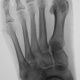

Травма.  Пациент направлен на рентгенографию стопы

P.S. похоже на костный островок

Не заметила ничего травматического...

Участок склероза или остеопойкилия.